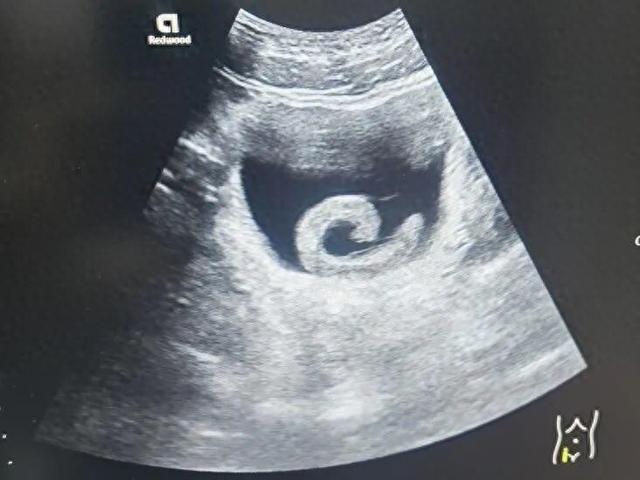

近日,网红“保罗在美国”因发布妻子生产视频引发争议,被指为了流量过度消费伴侣隐私。2月12日深夜,该网红委托律师发布声明称,深感愧疚与歉意,将暂停内容创作。网红“保罗在美国”在网上发布了其妻子生产过程的视频,称妻子三级撕裂、产后大出血